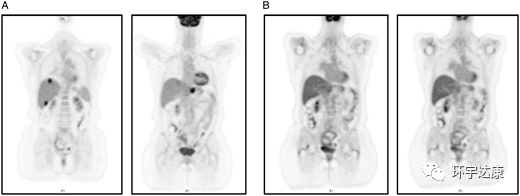

PET-CT扫描:(A)治疗前(B)拉罗替尼治疗后

因此如果患者一般状况良好,并且有可能接受治疗,那么进行二代测序[NGS]是值得的,并且应该检测TRK融合。